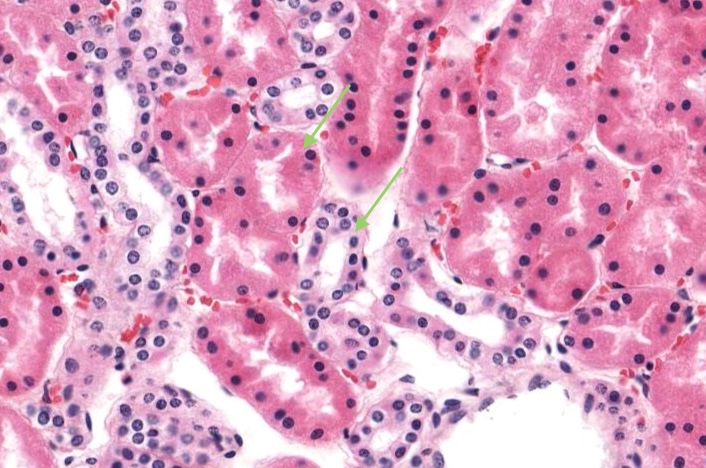

Collecting tubules traverse the cortical labyrinth only a short distance and then join collecting ducts in medullary rays. Their epithelial lining can be simple cuboidal or simple squamous in shape but they are easily distinguished from proximal convoluted tubules and distal convoluted tubules by visible cell boundaries between adjacent epithelial cells.

In the middle of each renal lobule are descending and ascending limbs of the nephron and a collecting duct. Collections of straight tubules and collecting ducts form the medullary ray within the cortex. The renal lobule is a cortical structure and nephrons in the same lobule drain into the collecting duct. Each interlobular artery branches into a number of afferent arterioles which each form a glomerulus, a capillary network and the efferent arteriole.